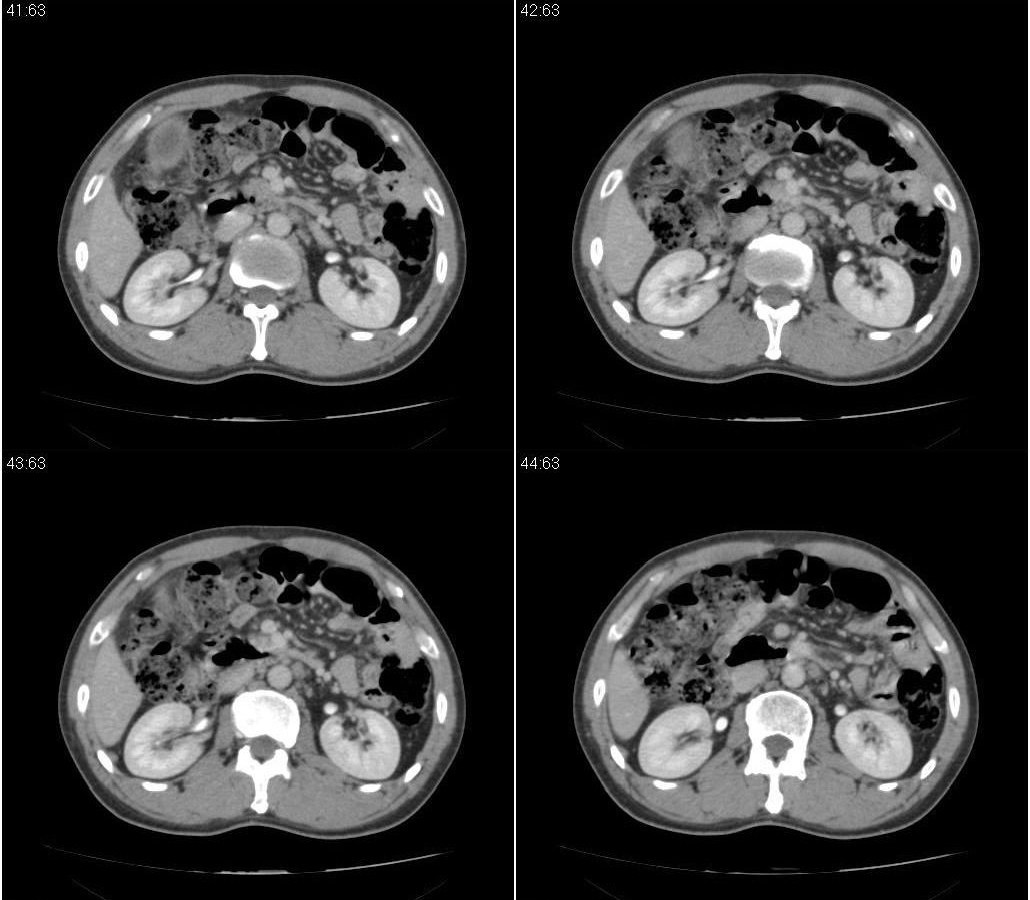

标题: CT21384:男性,50岁。发现无痛性黄疸十余天,B朝提示肝胆管 [打印本页]

标题: CT21384:男性,50岁。发现无痛性黄疸十余天,B朝提示肝胆管

1.考虑:壶腹占位病变(癌?)。

2.胆系低位梗阻:肝内外胆管扩张,胆囊增大,胰管扩张。

胰头癌伴低位胆道梗阻。

胆系低位梗阻(肝内外胆管扩张,胆囊增大,胰管扩张);考虑胰头癌或壶腹癌所致。

胰头强化欠均匀,胆胰管扩张。考虑胰头癌可能性大。

胆系低位梗阻(肝内外胆管扩张,胆囊增大,胰管扩张,钩突似有占位);考虑胰头癌